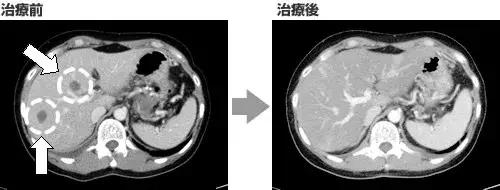

案例2

病名:胰腺癌晚期(胰腺尾),转移到肝脏,肺

患者:50岁女性

疗法:树突细胞疫苗+活化NK细胞

经过:第一次治疗结束后,CA19-9直接降到7355。第四次高度活化NK细胞治疗后,已降至141。

2016年底,复查的CT图像显示,肝部和肺支气管淋巴结等转移病灶已消失。原发部位的胰腺癌也缩小了大半。